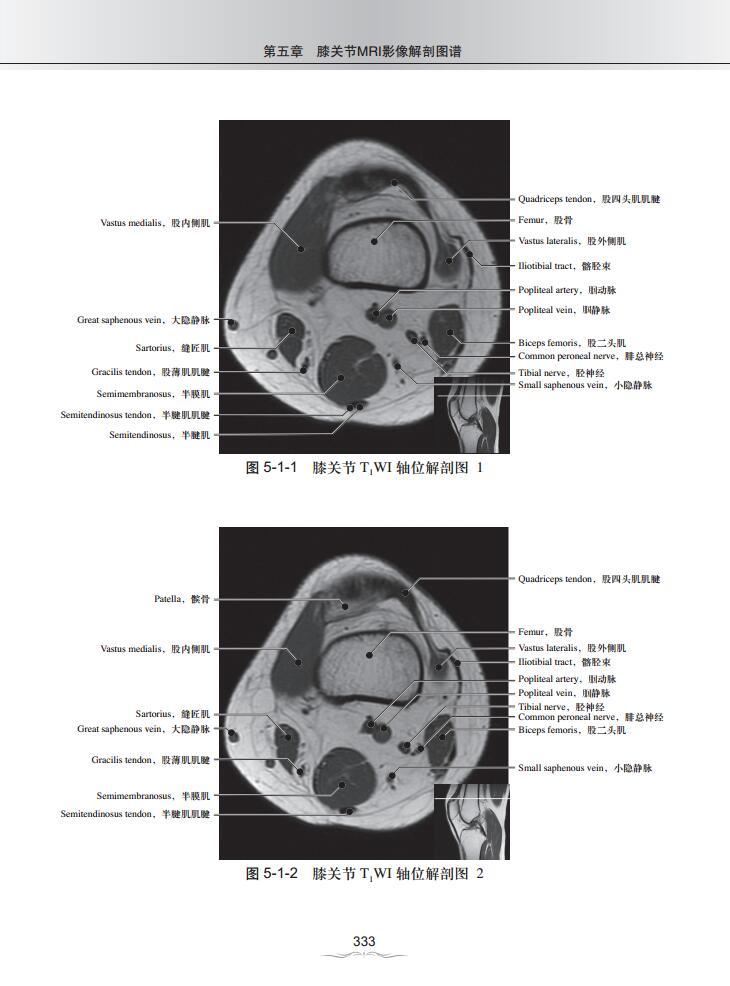

第五章 膝关节MRI影像解剖图谱

一、T1WI轴位解剖图